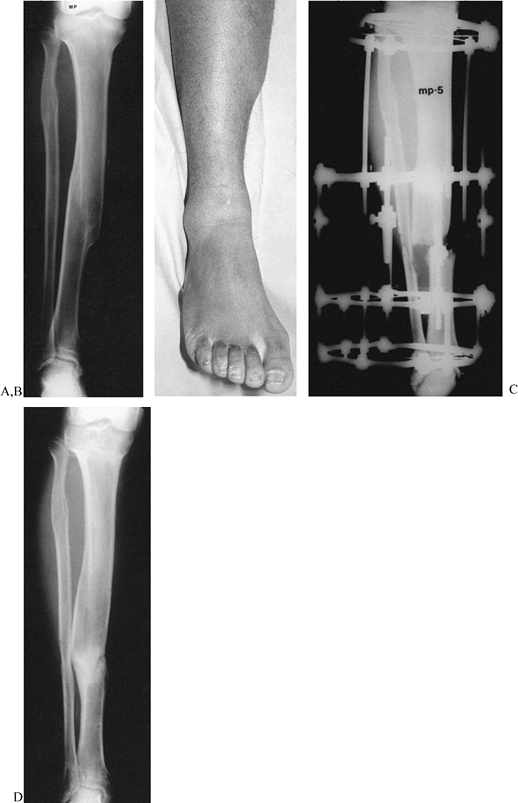

![]() |

Figure 32.26.

Varus malunions of the femur are illustrated with and without aggravating or compensatory translation. Notice that in the femur, translation toward the convexity is aggravating, whereas translation toward the concavity is compensatory. The reason for this is that by convention we refer to translation as the distal fragment being translated relative to the proximal. If we think of the proximal fragment of the femur as the one that is translating, then the rules are similar to that described in the tibia (Fig. 32.25). Notice that the translational deformity shifts the true apex of the deformity either proximal or distal to the apparent apex at the level of the malunion. |

Figure 32.27. A: Varus malunion of the mid diaphysis of the tibia with compensatory lateral translation. B:

The frame was applied with the hinges at the level of the true apex of the deformity, and the corticotomy was carried out at that level. C: Distraction of the concavity led to realignment of the tibia through an open-wedge correction. Notice the simultaneous correction of the angulation and translation, as demonstrated by the colinearity of the medial tibial diaphysis. The hinges are now straight and the rings are parallel, indicating completion of the deformity correction. D: After completion of the angular correction, the parallel rings were distracted to lengthen the tibia. E: Final AP standing radiograph demonstrates the alignment of the corrected malunion. There is a persistent leg-length discrepancy of 2 cm, which was accepted because of slow healing in this patient. |